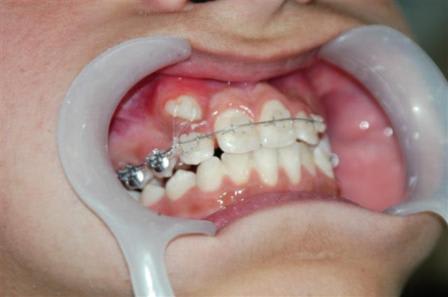

C'était ce matin, j'en ai profité pour faire ces photos à votre intention.

Des questions sur la procédure ?

Daniel